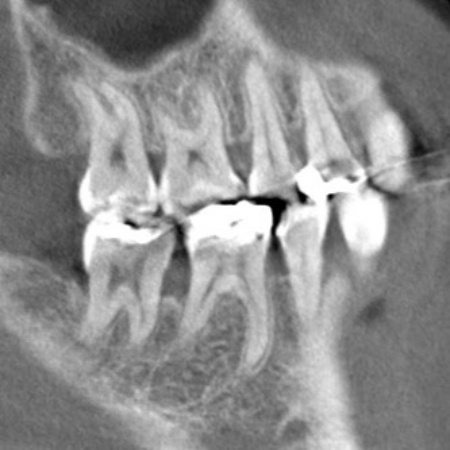

右上下の奥歯に対して、レントゲン撮影と歯間の溝の深さを測る歯周ポケット検査をしたところ、重度の歯周病が認められました。歯を支える骨が大幅に失われ、歯がぐらぐらしている状態です。

また左上下の奥歯についても同様で、重度の歯周病が進行しています。

続いて上下左右の奥歯に対して、失われた歯を支える骨や歯根膜(歯を支える薄い膜)を再生させるため、骨の再生を促す材料などを充填する歯周組織再生療法を実施しました。